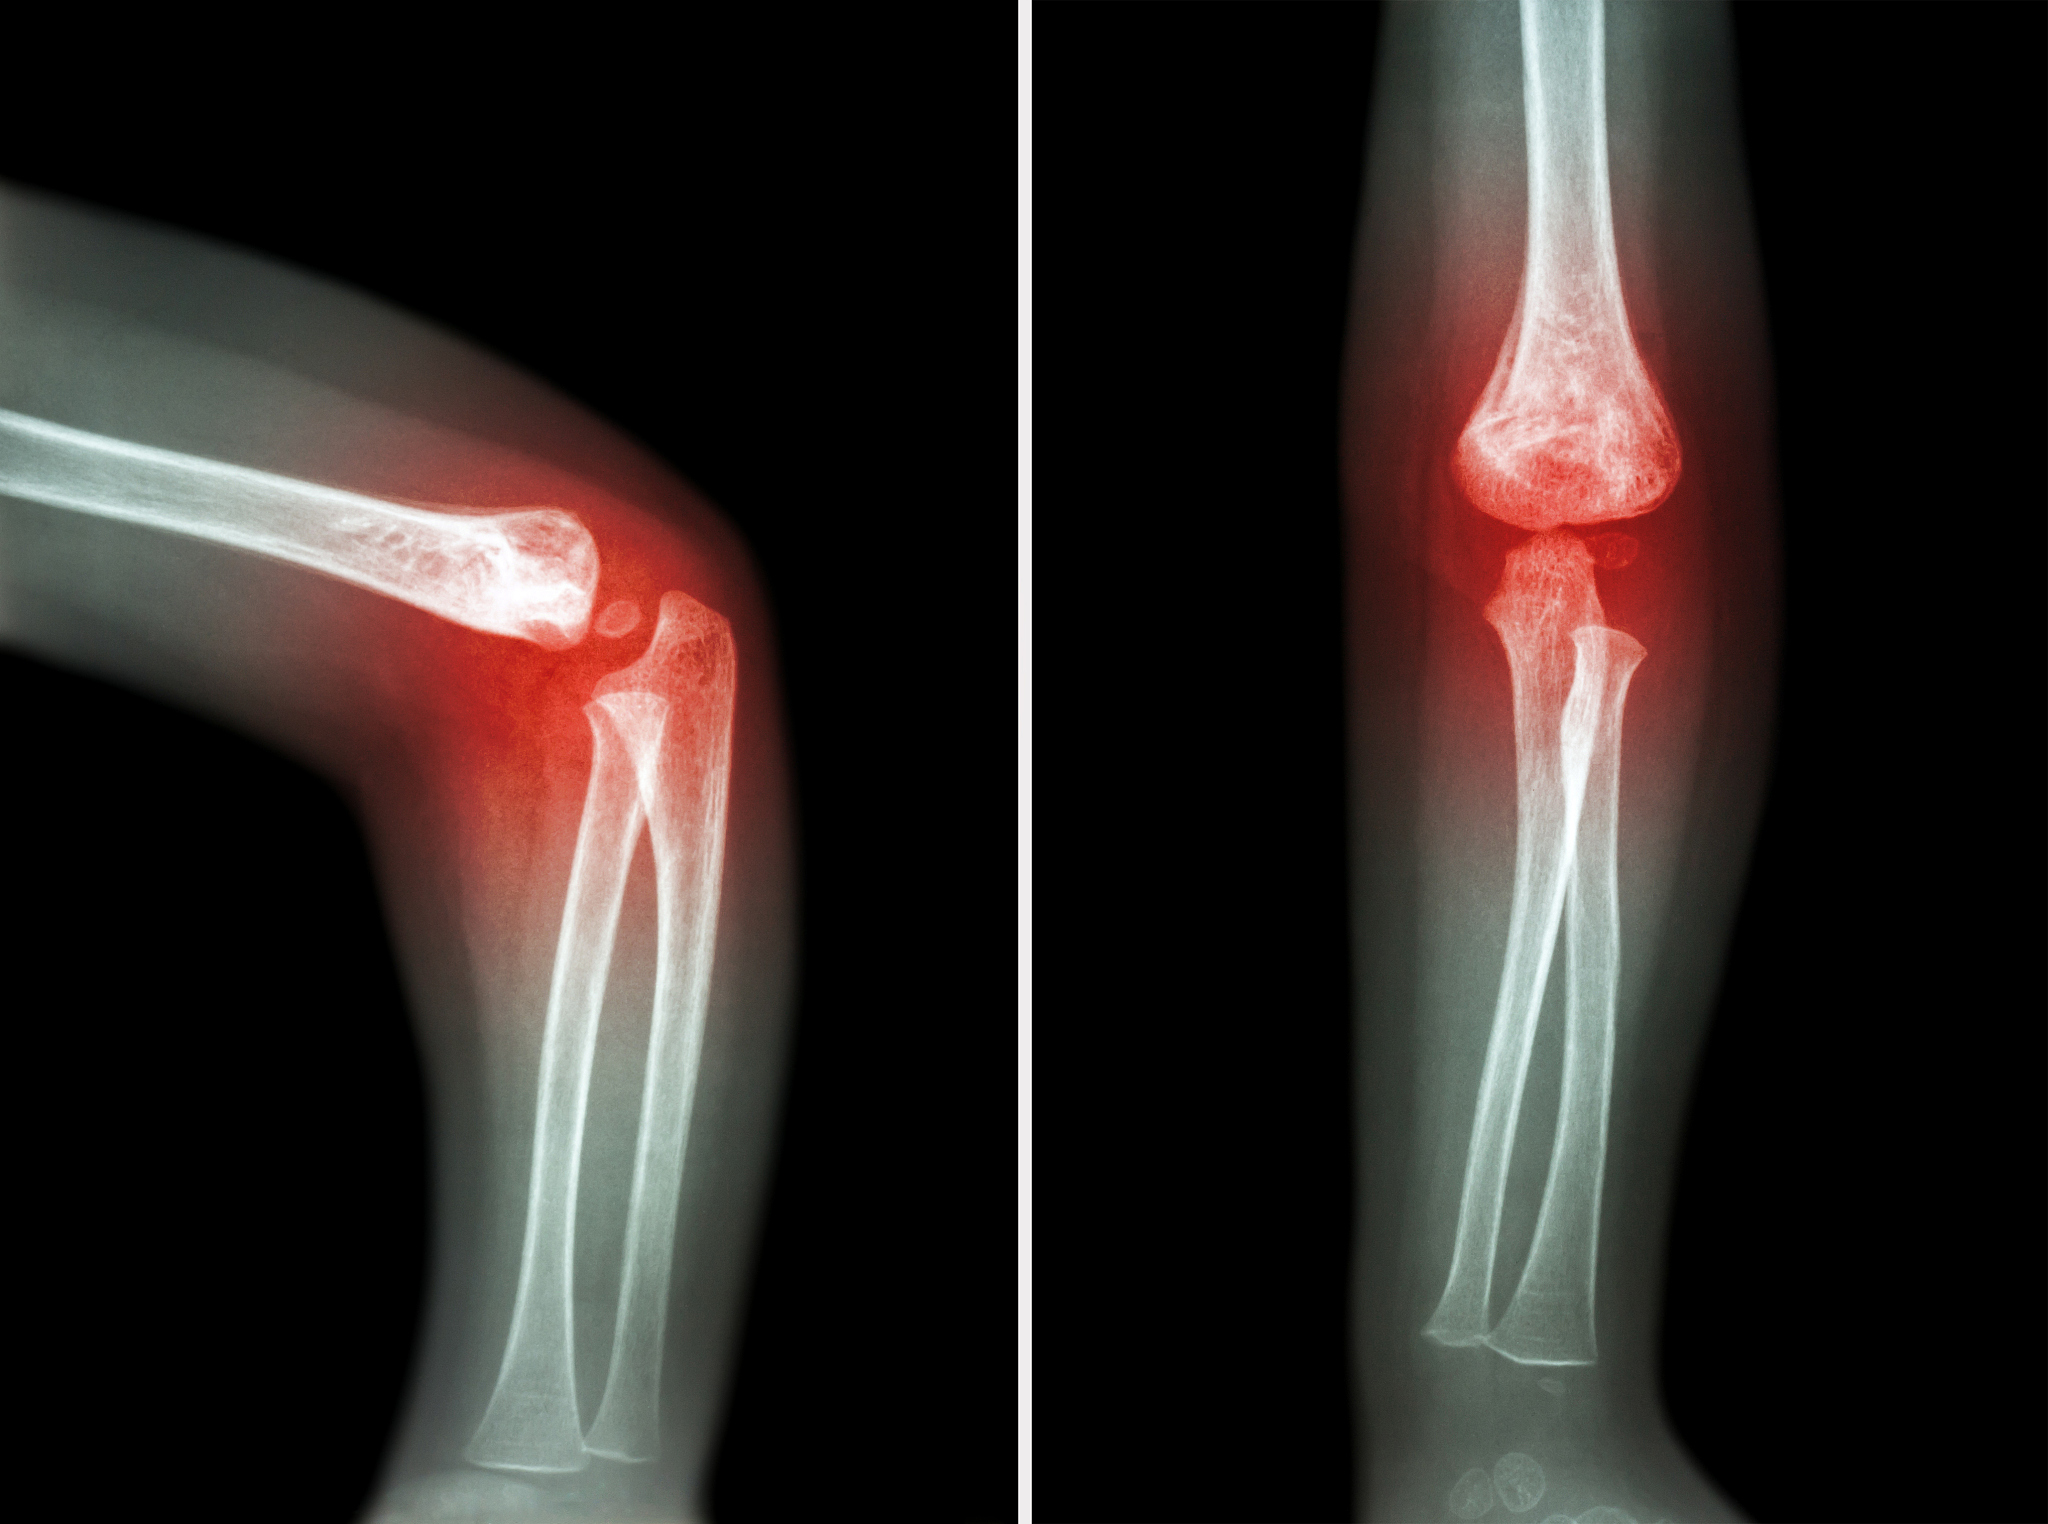

什么是骨关节炎?骨关节炎也称退行性关节病、骨质增生、骨关节病,是以关节软骨变性、破坏及骨质过度增生为特征的慢性关节病。主要表现为关节疼痛、僵硬、肥大及活动受限。一般认为与衰老、创伤、炎症、肥胖、代谢障碍和遗传等因素有关,好发于50岁以上中老年人。

什么是类风湿关节炎?类风湿关节炎是一种以侵蚀性、对称性、多关节炎为主要表现的慢性、全身性自身免疫性疾病,确切病因不明。基本病理改变为滑膜炎,表现双手近端的指间关节、掌指关节、腕、膝、足等关节的肿、痛,易反复发作,可引起关节软骨和骨破坏,延误治疗最终可导致关节畸形和功能丧失。